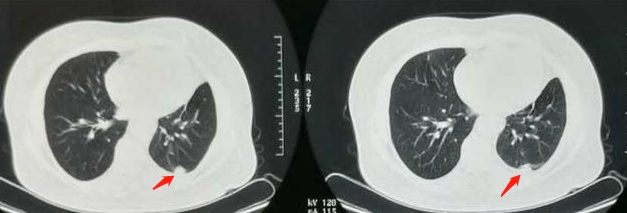

下图是一位52岁的老烟民,右侧小细胞肺癌,不能手术,也没有靶向药物可以使用,采用放化疗为主的综合治疗,第4年复查未见复发征象: